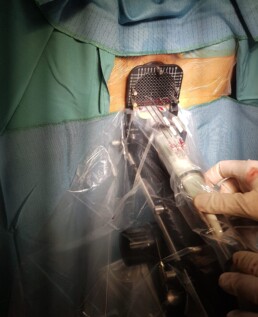

Beratung über Brachytherapie der Prostata

Mit der Bestrahlungstechnik von innen (LDR und HDR) schafft man Prostatakrebs direkt mit höherer Dosierung zu exponieren und gleichzeitig auf Risikoorganen (Blase, Harnröhre, Enddarm) mehr zu berücksichtigen um mögliche strahlenbedingte Reaktionen zu ersparen. In einer allgemeinen Narkose und Steinschnitlagerung werden Nadeln in Prostata platziert und danach entweder als LDR mir Radioaktiven Stäbchen-SEEDS mit ausprogramierten Aktivitätverlust (z.B. I-131 Halbwertszeit ca. 60 Tagen ) permanent beladen oder als HDR mit eine zwanzigminutige Kontaktbestrahlung über Schläuchen von Strahlen-Quelle (zB. Iridium-192) behandelt. Eine persönliche Beratung (angepasst an Tumorstadium, Risikostratifizierung, Prostatagröße, Blasenfunktion und Symptomen) und leitlinienkonforme optimierte Therapie (ob und welche Brachytherapie? LDR/HDR? kombinierte Brachy/Teletherapie? ) erhöhen Erfolgschancen. Nutzen Sie die Gelegenheit und lassen Sie fachlich beraten und, falls Sie für Brachytherapie geeignet sind, in der Klinik Donaustadt an Institut für Strahlentherapie-Radioonkologie spicken.